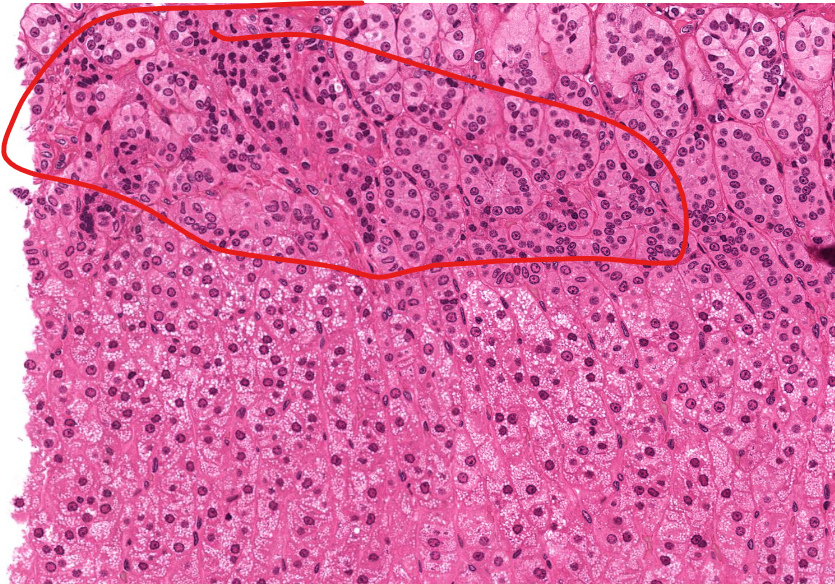

gastroesophageal junction

notice the shift from strat squamous to simple columnar (with long linear/coiled glands)

tissue type

simple columnar epi of the stomach